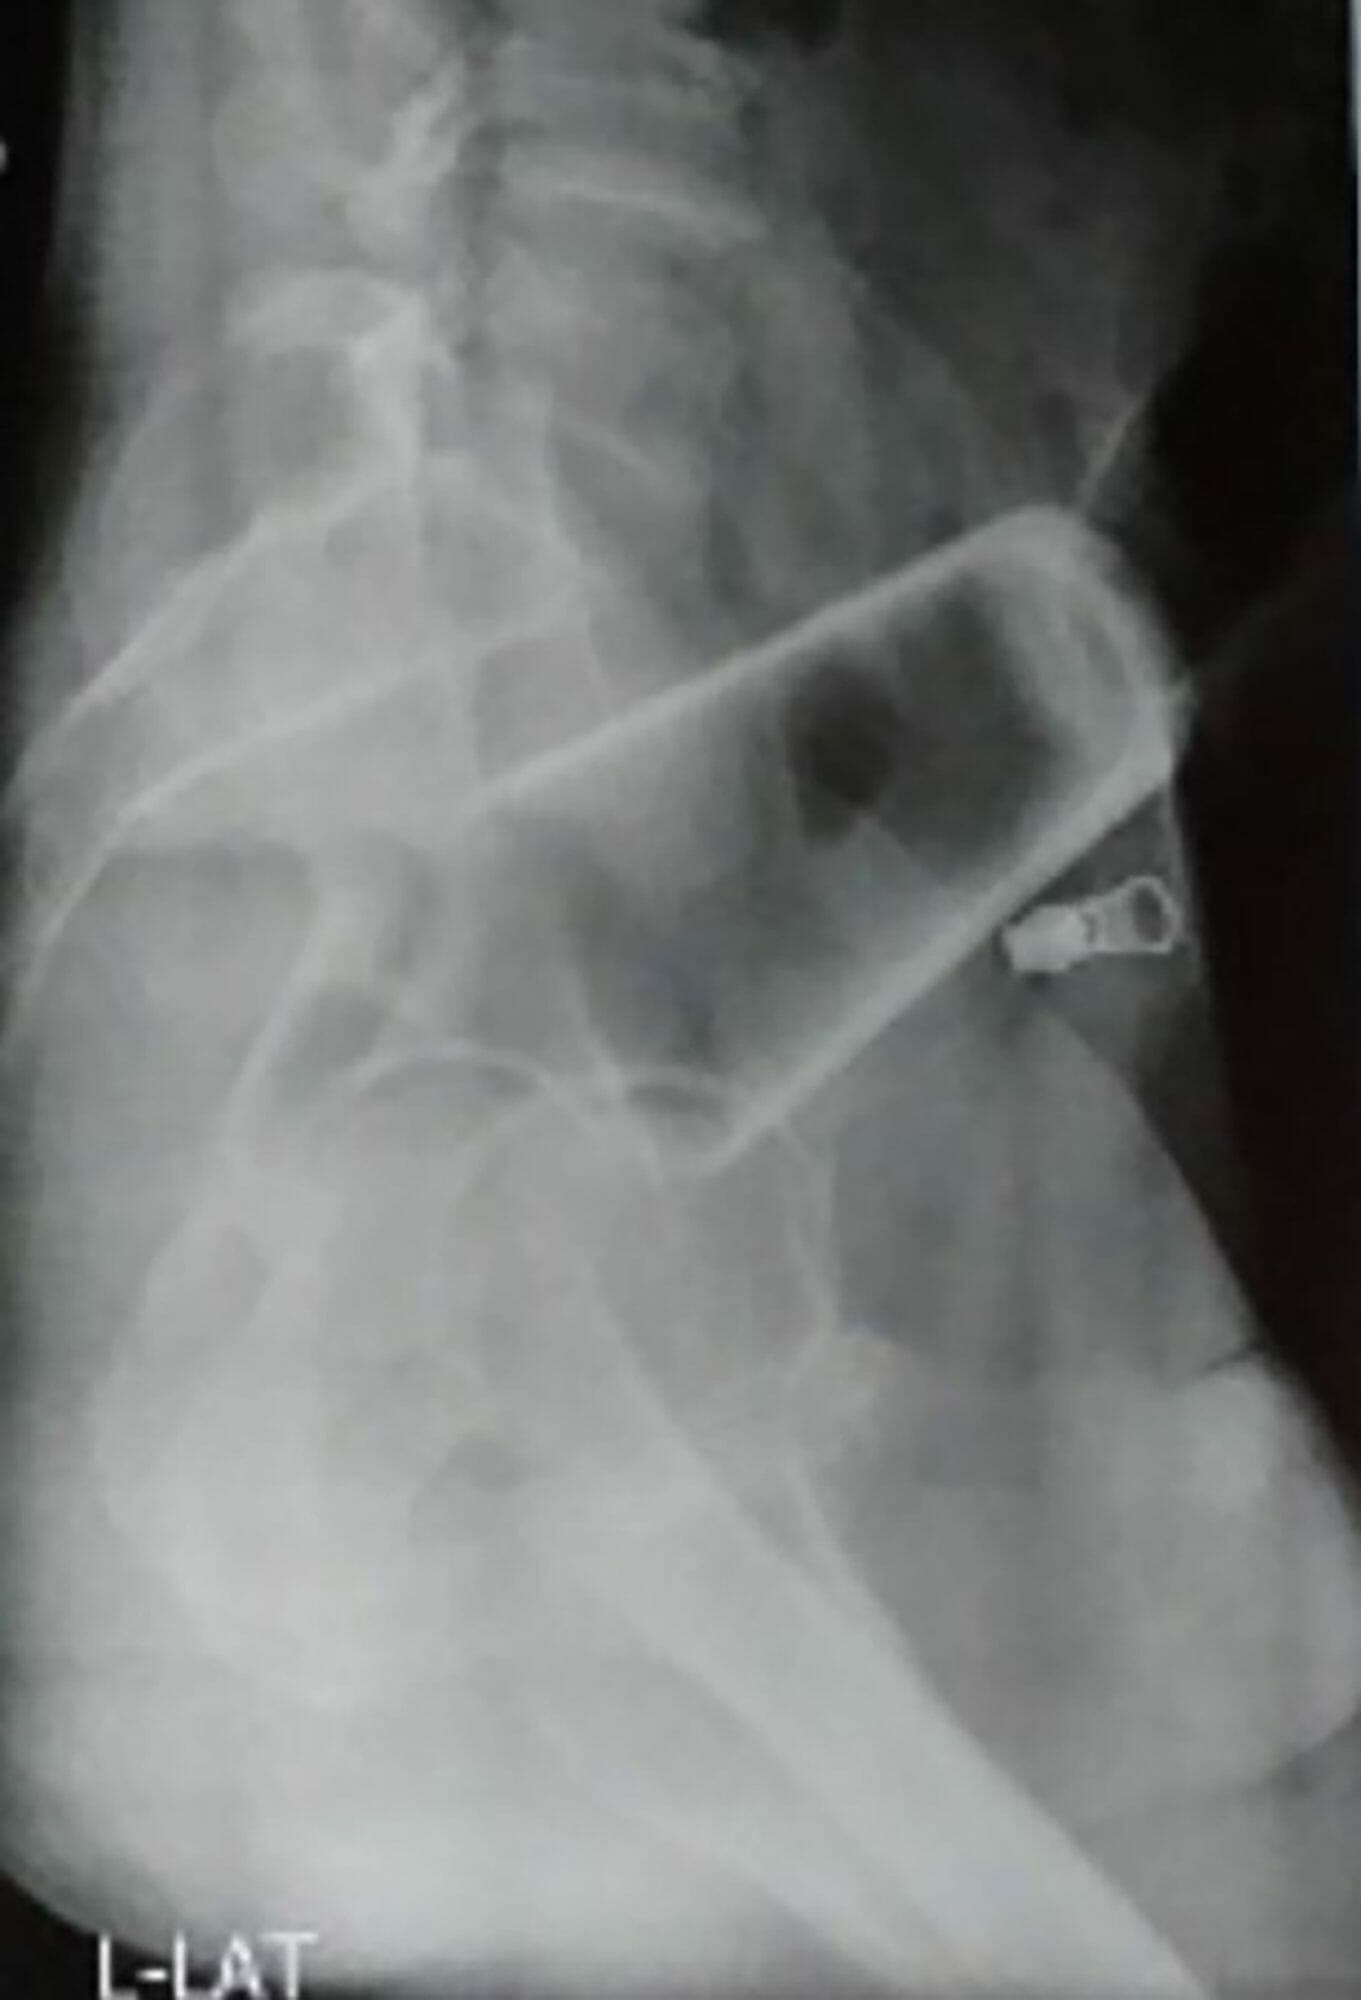

ولم تنجح جهوده الفردية لاستخراج الكأس الزجاجي، حيث كان الكأس مقلوبًا داخل المستقيم مما يعني أن الأطباء لم يتمكنوا من الإمساك به.

وقال تقرير المجلة: “تمت محاولة الحلب لإخراج الزجاج من خلال فتحة الشرج ، لكن هذا لم ينجح لأن الزجاج كان مرتفعًا ومقلوبًا ومثبتًا بإحكام ومن ثم تم إجراء فغر الأمعاء السيني واستخراج الزجاج.”